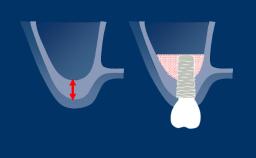

This concept is based on the biological phenomenon of osseointegration.

For a good long-term outcome of an implant-supported reconstruction, both hard and soft tissue need to be stable and to provide an adequate support for the prosthetic reconstruction.